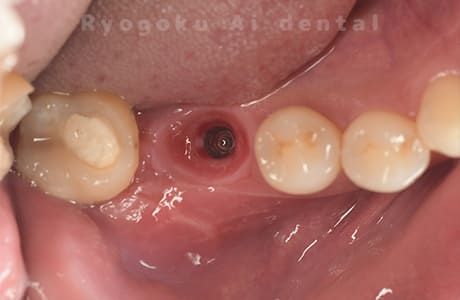

Case07

- 原因

- 右下6番歯根破折

-

- 治療内容

- インプラント治療

- 治療費用

- 約600,000円

右下の腫れが治らないとの事でご来院された患者様です。歯が割れていたため、抜歯を行い、骨に代わるお薬を入れ、インプラントを埋入致しました。経過良好で大変満足していただけました。

<リスク・副作用>

治療後、痛みや違和感、出血、腫れなどが出る事があります。喫煙者、糖尿病などの方の場合、歯が生着しない場合があります。